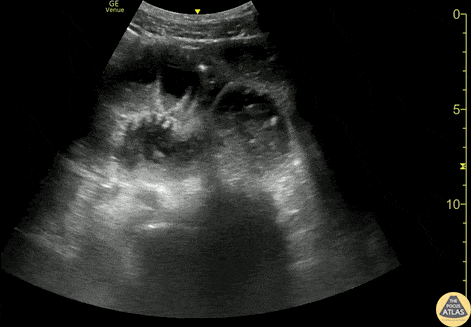

Bowel-GI - Small Bowel Obstruction

50s M with no surgical history presented with upper abdominal pain, biliary POCUS was performed which was negative, but large amounts of bowel gas were seen. Small bowel dilation was seen with multiple loops of bowel >2.5cm in diameter with bidirectional flow of bowel contents. CT confirmed SBO and the patient was taken to the OR for operative management Spencer Seballos MD, Resident, Denver Health Residency in Emergency Medicine Katie McCabe MD, Attending Physician, Denver Health Residency in Emergency Medicine